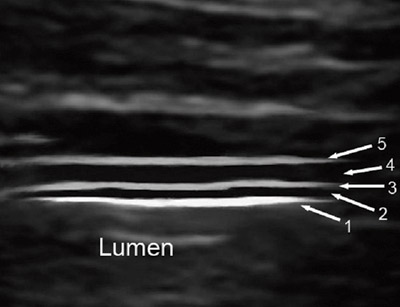

Med høyfrekvent ultrasonografi ses vanligvis fem lag i en normal tarmvegg (6, 7) enten man vurderer veggen fra serosa (transdusernære tarmvegg) eller fra mucosasiden (dorsale, transduserfjerne tarmvegg) (fig 1). Hvis det ses færre eller flere enn fem vegglag, kan dette indikere sykdom. For å undersøke om et tarmavsnitt er patologisk eller ikke, måles blant annet tarmveggens tykkelse. Lagdelingen i tarmveggen gjør at det oppstår overgangsekko når ultralydbølgene passerer fra et vegglag til et annet. Tykkelsen av tarmveggen måles oftest av den ventrale, transdusernære tarmveggen og vil da inkludere lagene 2 – 4, siden lag 1 i dette tilfellet er overgangsekkoet mellom lumen og mucosa. Overgangsekkoet mellom serosa og muscularis propria vil dessuten dekke en liten del av muscularis propria og således føre til at ventralsiden fremstår noe tynnere enn dorsalsiden med ultralyd. Siden dorsalsiden ofte er vanskelig å fremstille, velger man imidlertid ventralsiden som utgangspunkt for målingene.